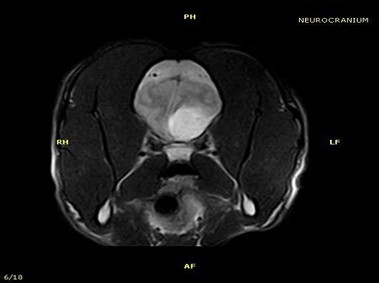

В настоящее время МРТ является наиболее предпочтительным методом визуализации любых мягких тканей, особенно для визуализации травм и патологий центральной нервной системы и суставов. Особенности Vet-MR позволяют использовать данный метод визуализации также в сфере ветеринарии.

Vet-MR специально разработана для визуализации небольших животных и является результатом внимания к деталям при разработке магнита, катушки и электронных компонентов, обеспечивая высокое качество экономически эффективной и простой в использовании МРТ в сфере ветеринарии.